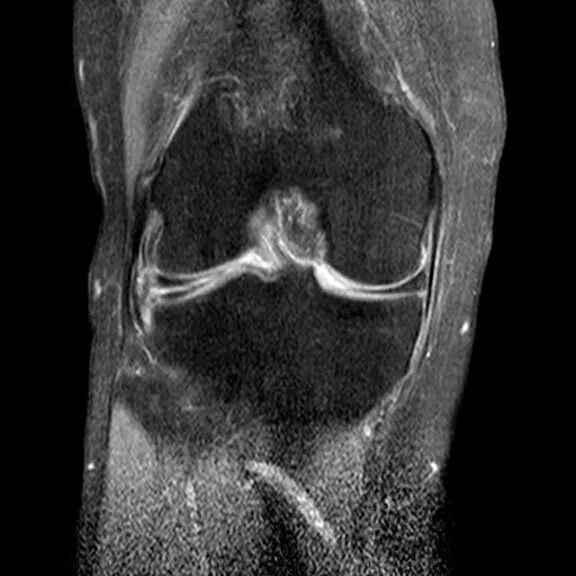

桶柄状撕裂MRI表现

1、宽度减小,在通过半月板体部的冠状面上蝶形消失,同时可见内移的半月板位于髁间窝、交叉韧带旁2、矢状面示残余的前角或后角变小或截断3、半月板前(后)角增宽或双半月板前(后)角征4、双前交叉韧带或双后交叉韧带征

桶柄状撕裂:半月板后角增宽